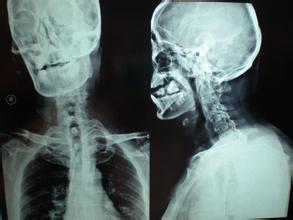

信号二、慢性发炎性下背痛:在临床上强直性脊柱炎患者出现了慢性背痛,这是患者最早的症状,在临床上具有一定的隐秘性,常常持续发生在3个月以上,并且患者在休息后会加重,在运动后减轻,并且在临床上出现了关节僵硬、髋部或是关节疼痛的症状,这些在临床上常常被患者忽视。